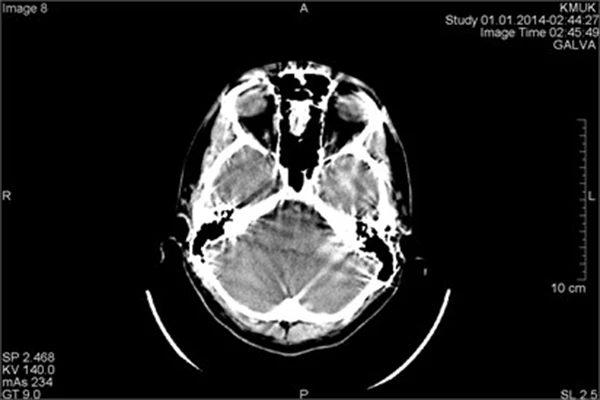

An Introduction to Computed Tomography (CT)

Learn how CT scanners use X-rays and computer processing to create detailed cross-sectional images.